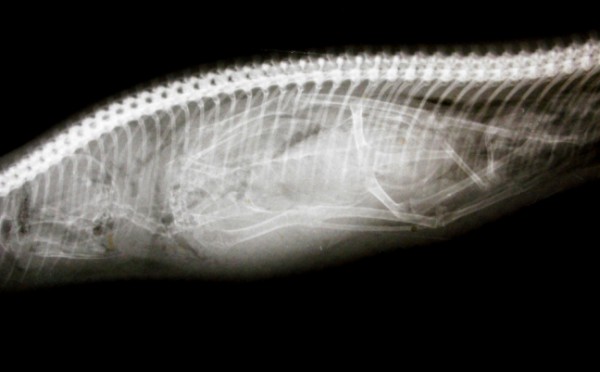

وأظهرت تلك الصور واللقطات صوراً بالأشعة السينية لبطون الحيوانات، أبرزها ابتلاع جرو صغير سكيناً طولها 120 سنتيمتراً؛ ما يوازي نحو 30 بوصة.

وأظهرت تلك الصور، التي التُقطت من قِبل مجموعة من الأطباء البيطريين، كيف أن الحيوانات تبتلع أحيانا أشياءً غريبة، مثل ابتلاع كلب آخر ضلع كامل لحيوان، فيما ابتلعت قطة أذرع تحكم "بلاي ستيشن".

وقال دكتور روبرت بليز، الذي يعمل بمركز الصحة الحيوانية في ولاية نيو جيرسي: "لقد طلبنا صاحب ثور اكتشف أن الحيوان يسعل ويكح خشباً، فوجدنا بالفحوص أنه ابتلع فرعاً كاملاً من السياج المحيط بالحظيرة، وأخرجناه بأعجوبة".